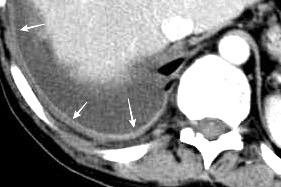

Colecciones “inflamatorias” abdominales llegan al tórax vía el hiato esofágico o por vía transdiafragmática

Afectación transdiafragmática: 5,6-43,7% de quistes hepáticos. “Área desnuda” del hígado.

Panda A et al. “Straddling Across Boundaries”. Thoracoabdominal Lesions: Spectrum and Pattern Approach. Curr Probl Diagn Radiol. 2015 Área desnuda. El hígado en contacto directo con el tendón central del diafragma. Contiene el hiato de VCI.

Pedrosa I et al. Hydatid Disease: Radiologic and Pathologic Features and Complications. Radiographics 2000